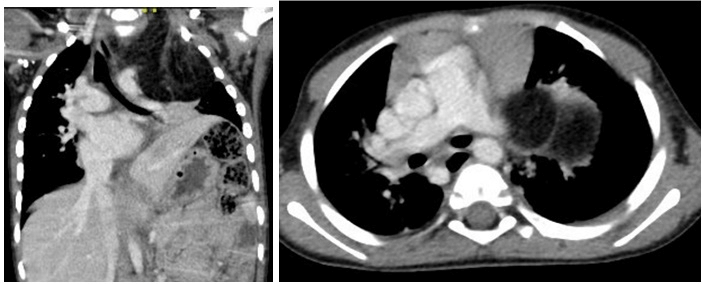

CT-scan showed a 5.1x7.2 cm fatty mass extending from the root of LT neck to the superior mediastinal (more on the LT side), displacement of the trachea towards the RT side with moderate narrowing of the tracheal lumen, the worst was noted at the level of the clavicle where the transverse diameter of the trachea was measured 3 mm. The mass also demonstrated anterior displacement of the common carotid artery and posterior displacement of the LT subclavian artery with immediate contact with the posterior part of the aortic arch (Figures 3A & 3B).

Figure 3: A) Coronal CT-scan image showing upper anterior mediastinal mass, trachea compression and deviation to RT side B) Axial CT-scan image showing the lower end of the mass extended down below the level of tracheal bifurcation.